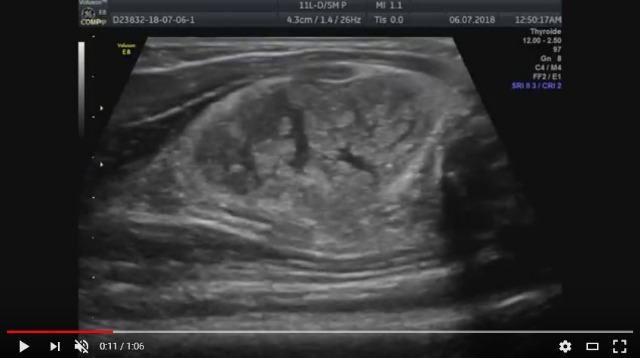

Похожа на гемангиому? А если нет, то на что похожа?

Локализация опухоли в данном случае другая, просто похожая структура на УЗИ.

Мне кажется, что больше похоже на опухоль "мышечного происхождения", а не "сосудистого"

Против гемангиомы говорит наличие четкой капсулы у образования и стволовой тип васкуляризации, что не характерно для гемангиом и напротив характерно для рабдомиомы. При саркоме также не бывает такой четкой и главное целой капсулы. Хотя малигнизацию рабдомиомы исключить нельзя.